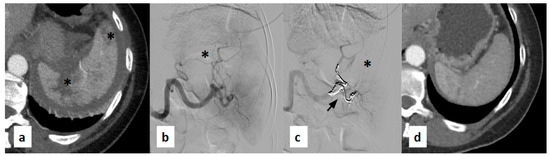

2.3. SAE Procedure

3.1. Embolization Technique and Agents Used